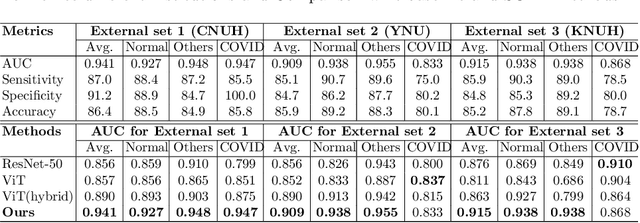

Abstract:Developing a robust algorithm to diagnose and quantify the severity of COVID-19 using Chest X-ray (CXR) requires a large number of well-curated COVID-19 datasets, which is difficult to collect under the global COVID-19 pandemic. On the other hand, CXR data with other findings are abundant. This situation is ideally suited for the Vision Transformer (ViT) architecture, where a lot of unlabeled data can be used through structural modeling by the self-attention mechanism. However, the use of existing ViT is not optimal, since feature embedding through direct patch flattening or ResNet backbone in the standard ViT is not intended for CXR. To address this problem, here we propose a novel Vision Transformer that utilizes low-level CXR feature corpus obtained from a backbone network that extracts common CXR findings. Specifically, the backbone network is first trained with large public datasets to detect common abnormal findings such as consolidation, opacity, edema, etc. Then, the embedded features from the backbone network are used as corpora for a Transformer model for the diagnosis and the severity quantification of COVID-19. We evaluate our model on various external test datasets from totally different institutions to evaluate the generalization capability. The experimental results confirm that our model can achieve the state-of-the-art performance in both diagnosis and severity quantification tasks with superior generalization capability, which are sine qua non of widespread deployment.

Abstract:Under the global COVID-19 crisis, developing robust diagnosis algorithm for COVID-19 using CXR is hampered by the lack of the well-curated COVID-19 data set, although CXR data with other disease are abundant. This situation is suitable for vision transformer architecture that can exploit the abundant unlabeled data using pre-training. However, the direct use of existing vision transformer that uses the corpus generated by the ResNet is not optimal for correct feature embedding. To mitigate this problem, we propose a novel vision Transformer by using the low-level CXR feature corpus that are obtained to extract the abnormal CXR features. Specifically, the backbone network is trained using large public datasets to obtain the abnormal features in routine diagnosis such as consolidation, glass-grass opacity (GGO), etc. Then, the embedded features from the backbone network are used as corpus for vision transformer training. We examine our model on various external test datasets acquired from totally different institutions to assess the generalization ability. Our experiments demonstrate that our method achieved the state-of-art performance and has better generalization capability, which are crucial for a widespread deployment.